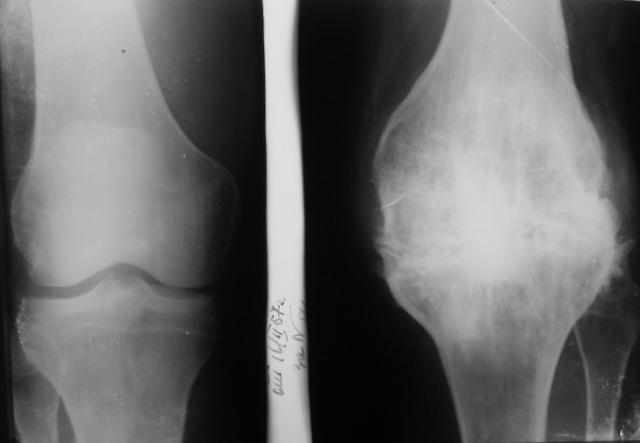

Рентгеновские снимки анкилоза суставов: Как это выглядит